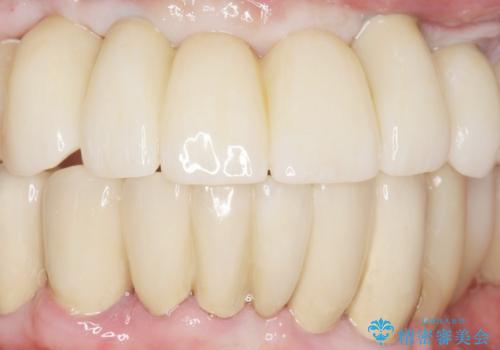

当初は上顎③2①12③ブリッジの予定でしたが、リカバリー手術後上顎3②11②③ブリッジによる補綴を行いました。

リカバリー手術により無事に治療が終わりご安心頂けました。

再開してしまった喫煙をやめて頂いたおかげで経過は順調ですが、定期健診の際には禁煙の確認と注意喚起をさせて頂く予定です。